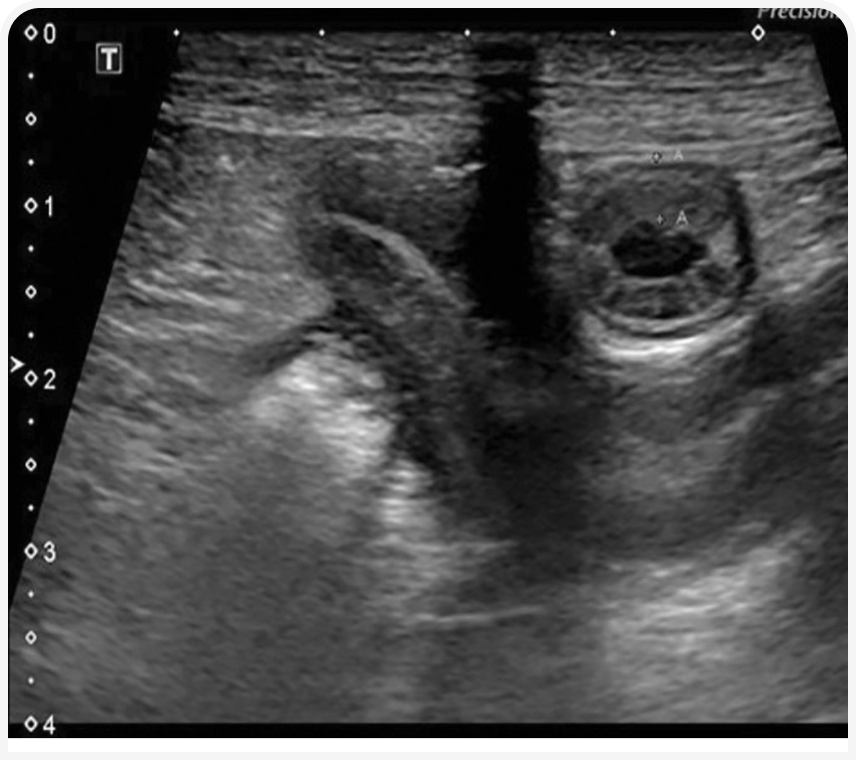

Чаще всего ЭПБ у собак обусловлена хронической воспалительной энтеропатией и лимфангиэктазией кишечника.